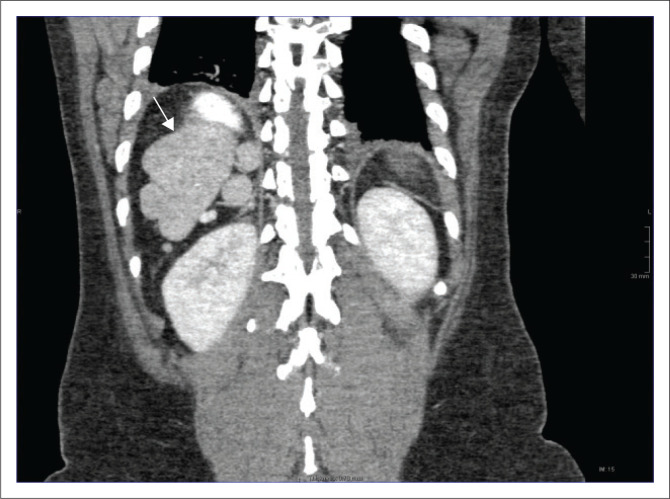

Heterotaxy syndrome, also known as situs ambiguous, is a spectrum of pathology due to loss of the normal right-to-left asymmetry of the thoraco-abdominal organs. This report describes the case of a 39-year-old female, previously well, who presented with bowel obstruction. CT showed features of left isomerism, with malrotation and volvulus.

Contribution: Heterotaxy syndrome consists of cardiac and non-cardiac manifestations. Imaging studies play a crucial role in the individualised management of the patient.